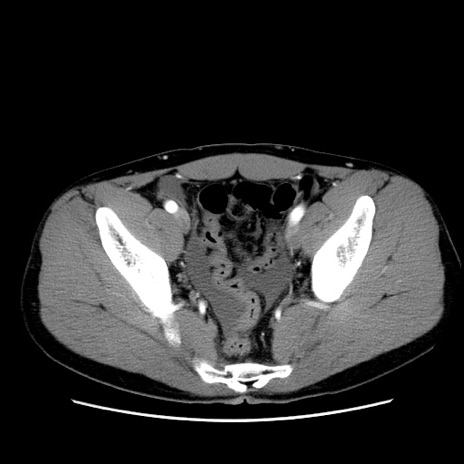

症例36(横断像)

【症例】20歳代 男性

【主訴】心窩部痛

【現病歴】今朝より上腹部痛あり。一旦軽快していたが再度出現したため救急要請。昨日夕に白身の魚を含む刺身を食べた。

【身体所見】BP 136/89mmHg、HR 74/min、BT 37.0℃、腹部:膨満、軟、心窩部に圧痛あり。反跳痛なし、筋性防御なし、腸雑音やや亢進あり。

【データ】WBC 17700、CRP 0.48